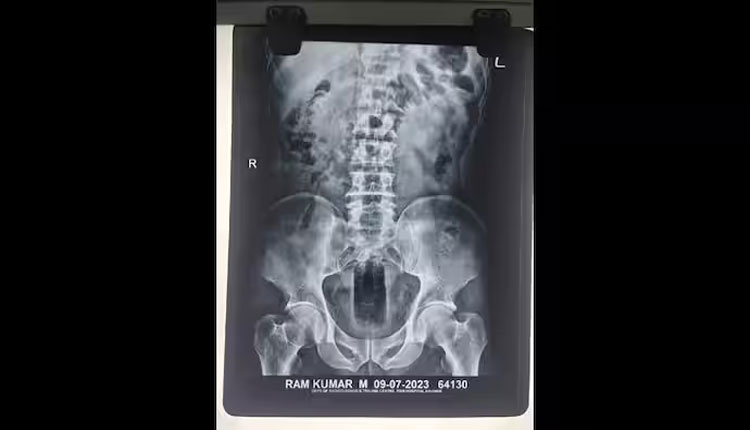

ଜୟପୁର: ଏକ ଆଶ୍ଚର୍ଯ୍ୟଜନକ ଖବର ରାଜସ୍ଥାନର ବିକାନେର ସହରରୁ ଆସିଛି। ବିକାନେରରେ ରହୁଥିବା ରାମ କୁମାରଙ୍କର ଏକ୍ସ-ରେ ରିପୋର୍ଟ ପରେ ହୋଇଥିବା ଅପରେସନକୁ ନେଇ ଏବେ ଚର୍ଚ୍ଚା ଚାଲିଛି। ଶ୍ରମିକ ଭାବରେ କାର୍ଯ୍ୟ କରୁଥିବା ୟୁପିର ଏହି ମୂଳ ବାସିନ୍ଦା ରାମ କୁମାର ତିନି ଦିନ ହସ୍ପିଟାଲରେ ଭର୍ତ୍ତି ହୋଇଛନ୍ତି। ଅଣ୍ଟାରେ ଯନ୍ତ୍ରଣା ହେଉଥିବାରୁ ହସ୍ପିଟାଲରେ ଭର୍ତ୍ତି ହୋଇଛନ୍ତି।

ତେଣୁ ଡାକ୍ତର ପ୍ରଥମେ ତାଙ୍କର ଏକ୍ସ-ରେ କରାଇ ରିପୋର୍ଟ ମାଗିଥିଲେ। ଏକ୍ସ-ରେ ରିପୋର୍ଟ ପରେ ଆସିବା ପରେ ତାଙ୍କ ଗୁପ୍ତାଙ୍ଗରୁ ଡାକ୍ତରୀ ଟିମ୍ ଏକ ସାତ ଇଞ୍ଚ ଲମ୍ବା ଏବଂ ତିନି ଇଞ୍ଚ ଚଉଡା ପ୍ଲାଷ୍ଟିକ୍ ବୋତଲ ବାହାର କରିଥିଲେ। ଏବେ ତାଙ୍କ ସ୍ବାସ୍ଥ୍ୟାବସ୍ଥା ସ୍ଥିର ରହିଛି। ଘଟଣା ଆଶ୍ଚର୍ଯ୍ୟଜନକ ଅଟେ। ଜେଏନଭିସି ପୋଲିସ ଏହି ଘଟଣାର ତଦନ୍ତ କରୁଛି।

ବିକାନେରରେ, ଷଡଯନ୍ତ୍ରକାରୀମାନେ ଯୁବକଙ୍କର ବ୍ୟକ୍ତିଗତ ଅଙ୍ଗରେ ଏକ ପ୍ଲାଷ୍ଟିକ୍ ବୋତଲ ପୂରାଇ ଦେଇଥିଲେ। ମିଳିଥିବା ସୂଚନା ଅନୁସାରେ ନିକଟରେ କୌଣସି କାରଣରୁ ରାମ କୁମାରଙ୍କୁ ବିକେନାରର ସ୍ଥାନୀୟ ଲୋକେ ପିଟିପିଟି ହତ୍ୟା କରିବାକୁ ଉଦ୍ୟମ କରିଥିଲେ।

ଏହି ସମୟରେ ସ୍ଥାନୀୟ ଲୋକେ ତାଙ୍କ ଗୁପ୍ତାଙ୍ଗରେ ପ୍ରାୟ ସାତ ଇଞ୍ଚ ଲମ୍ବ ଏବଂ ତିନି ଇଞ୍ଚ ଚଉଡା ବୋତଲ ଭର୍ତ୍ତି କରି ଦେଇଥିଲେ। ଏହାପରେ ସେ କୌଣସି ପ୍ରକାରେ ଘରେ ପହଁଚିଥିଲେ। ଏହି ସମୟରେ ତାଙ୍କ ଅଣ୍ଟା ତଳେ ଅଧିକ ଯନ୍ତ୍ରଣା ହୋଇଥିଲା। ତେବେ ଡାକ୍ତରଖାନା ନିଆଯିବା ପରେ ତାଙ୍କୁ ଅଧିକ ଚିକିତ୍ସା କରାଯାଇଛି। ଏକ୍ସ-ରେ ଦେଖିବାକୁ ମିଳିଥିଲା ​​ଯେ ତାଙ୍କ ସହ ହିଂସା ହୋଇଛି। ତାଙ୍କ ବୟାନ ରେକର୍ଡ କରିବା ପରେ ବର୍ତ୍ତମାନ ମାମଲା ରୁଜୁ ପାଇଁ ପ୍ରସ୍ତୁତି ଚାଲିଛି।